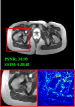

Figure 5 provides the qualitative comparison of the various methods on the four datasets at a scale of 4. The top, second, third, and bottom rows are the SR results under the FastMRI, clinical brain, clinical tumor and clinical pelvic datasets, respectively. The red boxes indicate the zoom-in region of complicated anatomical structures along with their corresponding error maps. Note that the brighter textures in the error maps, the lower the quality of the reconstructed images. As can be seen, compared to methods based on Transformers and CNNs, diffusion-based methods like DisC-Diff and DiffMSR (Ours) are capable of reconstructing high-realistic images with promising reconstruction metric scores (PSNR and SSIM). Nevertheless, while DisC-Diff can reconstruct high-precision MR images, it does not preserve the structure present in the original HR images, introducing some additional information that can affect medical diagnosis. In contrast, our method combines DM and PLWformer, which can preserve the original image’s structure while restoring high-frequency information.

In Table 1, we provide a comprehensive quantitative analysis, comparing our DiffMSR with other state-of-the-art MCSR methods on four datasets with a 4 upscaling factor. As we can see, our DiffMSR performs best among all comparison methods in terms of PSNR and SSIM metrics in all MRI datasets. Specifically, we notice that the performance of CNN-based methods is relatively poor as CNNs struggle to capture long-range dependencies. Although Transformer-based methods address some of the issues with CNNs, the ability of Transformers to reconstruct high-frequency details is limited, restricting further improvements in metrics. The DisC-Diff method based on DM achieves high metric values, as DM can generate some high-frequency details, but it also introduces unnecessary information. Our proposed DiffMSR combines the strengths of Transformer and DM, preserving the original image structure while maximizing the reconstruction of complicated anatomical structures, obtaining the best performance.

In this section, we present more visual qualitative comparisons. Figures 8, 9, 10, and 11 show the reconstruction results of each method in FastMRI, clinical brain, clinical tumor, and clinical pelvic, respectively. As can be seen, although DisC-Diff can reconstruct MR images with high-frequency information, it fails to preserve the structure and content of the original Target HR image effectively, resulting in image distortion. In contrast, our proposed DiffMSR can restore high-frequency information while preserving the structure of the original HR image, indicating the effectiveness of the joint use of DM and PLWformer.